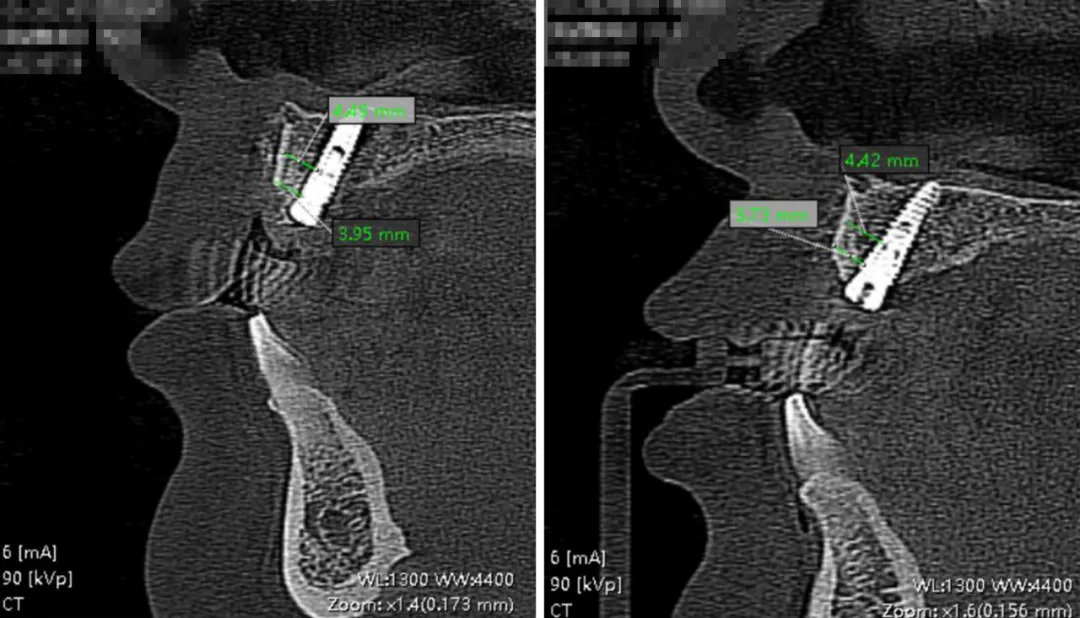

影像学检查

术前与术后影响对比,骨片的屏障维持效果理想,颊舌向骨量宽度维持在 10.35mm 左右

11 牙位屏障维持稳定,8 个月时水平向骨量维持在 4.5mm 左右

21牙位屏障维持稳定,8 个月时水平向骨量维持在 3.8mm 左右